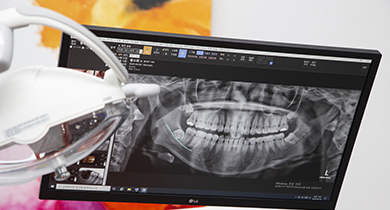

치아 및 잇몸상태 체크